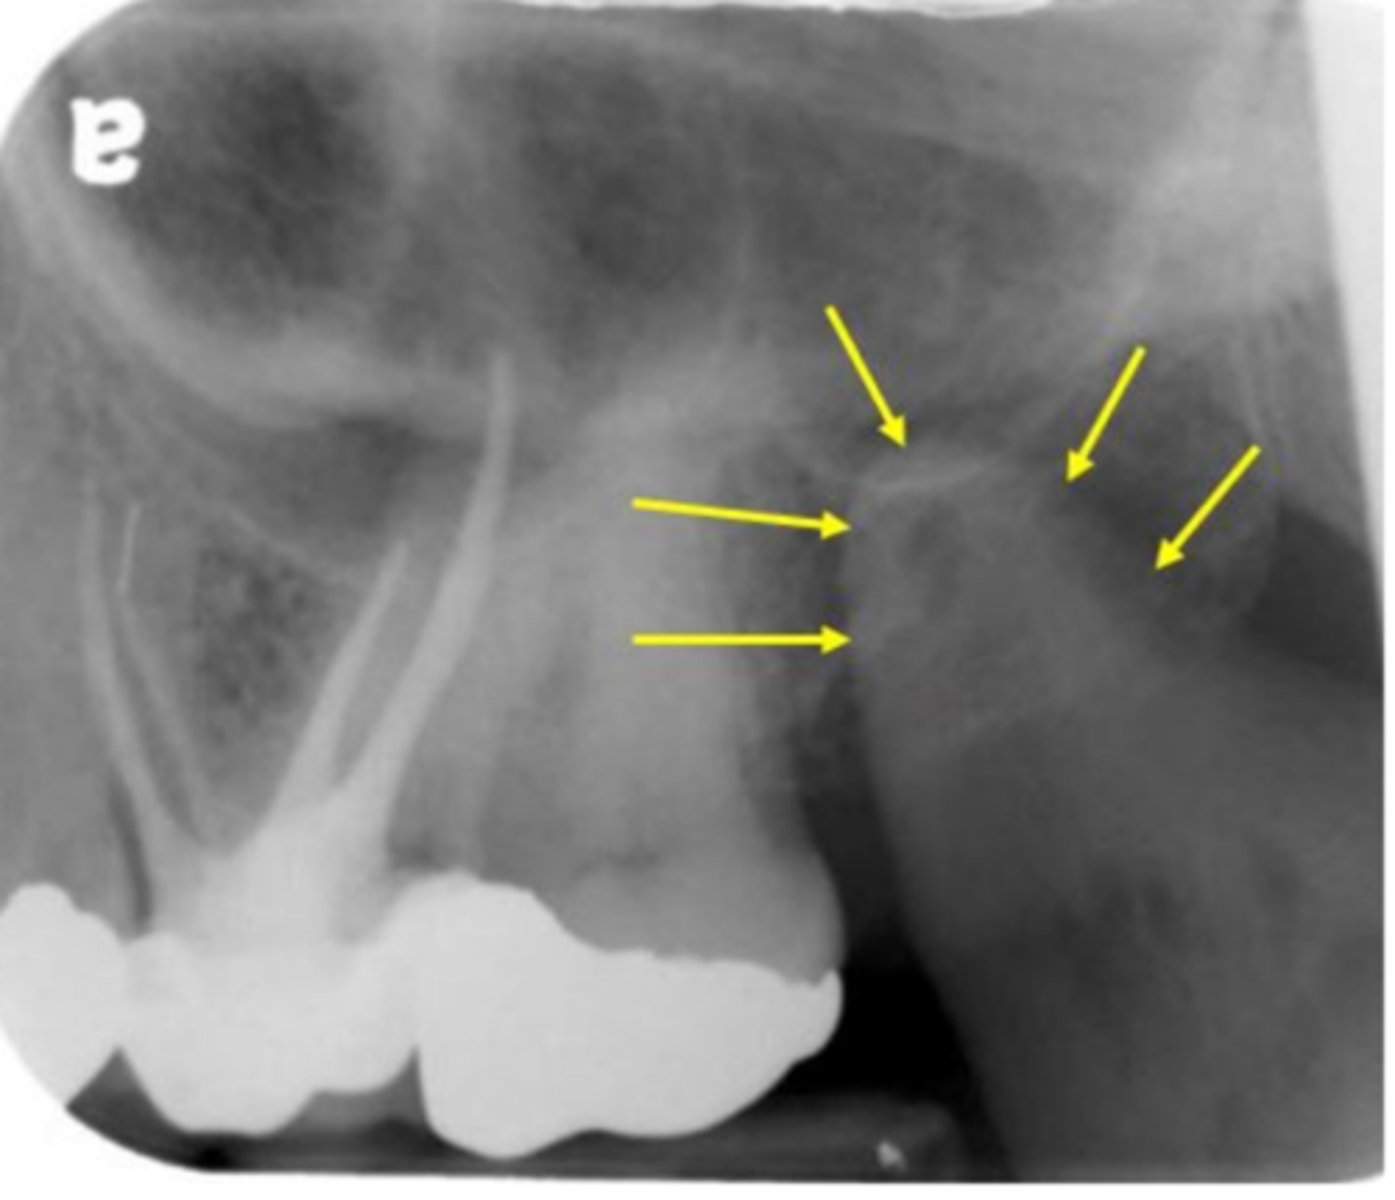

anterior border of the ramus

Name the structure the white arrow is pointing to.

internal oblique ridge or mylohyoid ridge

Name structure the black arrow is pointing to.

Submandibular fossa

Name the radiolucent area indicated by the arrows